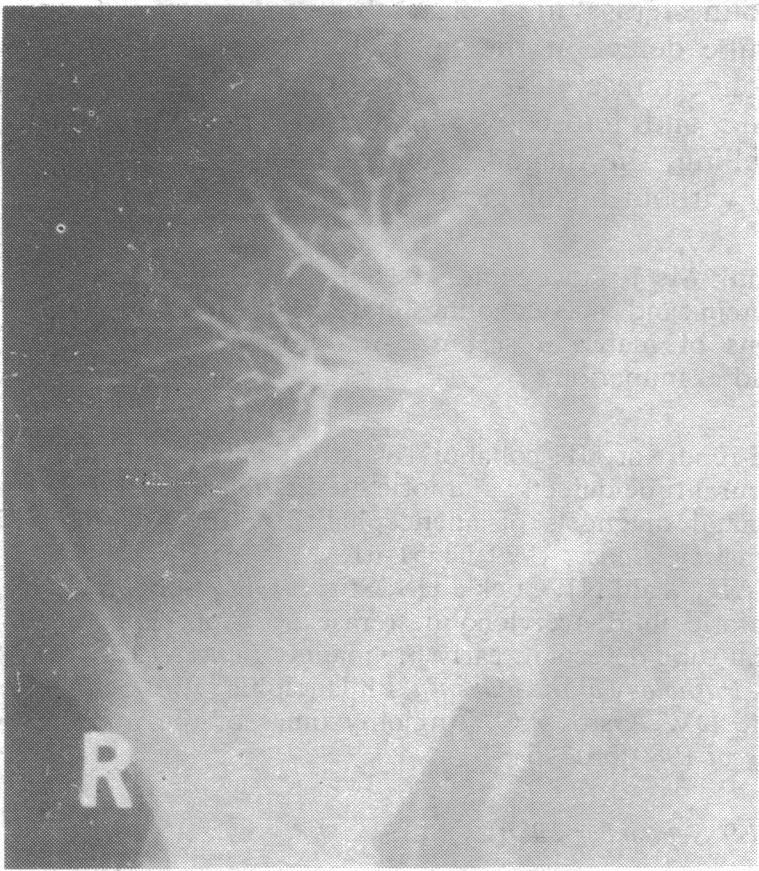

Rejection of renal transplants: a further cause of intrarenal aneurysms.

Renal artery aneurysms: an angiographic sign of transplant rejection.

Renal aneurysms in rejected renal transplants.

Renal transplant rejection and aneurysm formation.